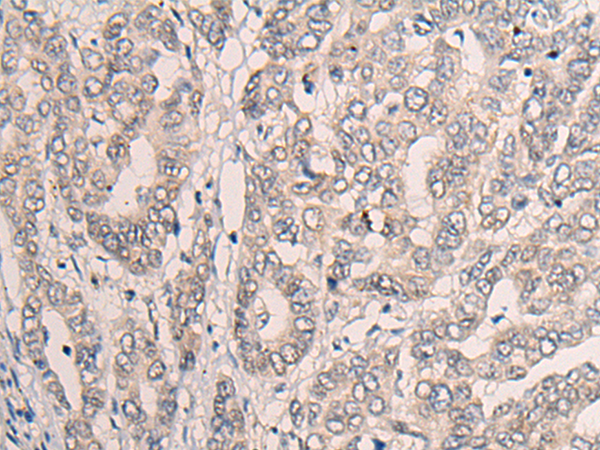

IHC positive control: |

Human liver cancer |